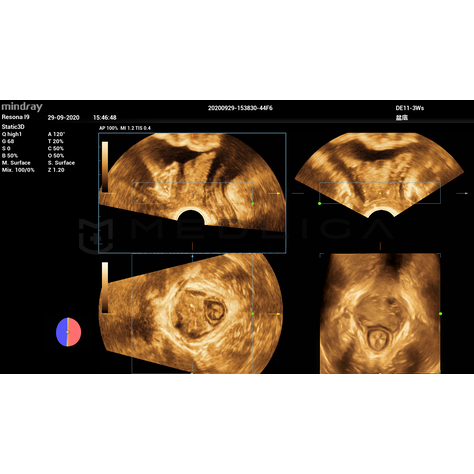

Программное обеспечение для автоматических измерений параметров и оценки функции мышц тазового дна.

Smart Pelvic - новое решение, позволяющее значительно упростить диагностическую процедуру и свести к минимуму время исследования функций мышц тазового дна. Благодаря чрезвычайно простому пользовательскому интерфейсу, программа генерирует стандартную систему координат и автоматически просчитывает все связанные измерения в течение нескольких секунд.